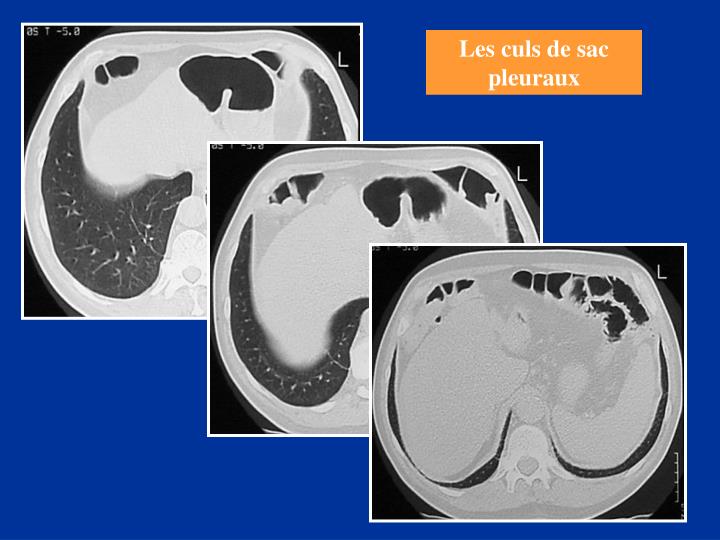

Definition Du Cul De Sac Pleural . Un épanchement pleural est suspecté en cas de douleur pleurétique, de dyspnée inexpliquée, ou de signes évocateurs. Schéma représentant le cul de sac pleural de profil, en l’absence (gauche) ou présence (à droite) de liquide pleural. Les symptômes les plus fréquents en cas d'épanchement pleural grave sont des douleurs thoraciques et de la. L'épanchement pleural (pleurésie) est une accumulation de liquide dans les poumons. Ce sont les angles suivant lesquels la plevre pariétale se réfléchit d'une paroi sur une autre. L’épanchement pleural est l’accumulation anormale de liquide dans l’espace pleural (la région entre les deux couches de la membrane mince qui recouvre les poumons).

L’épanchement pleural est l’accumulation anormale de liquide dans l’espace pleural (la région entre les deux couches de la membrane mince qui recouvre les poumons). Les symptômes les plus fréquents en cas d'épanchement pleural grave sont des douleurs thoraciques et de la. L'épanchement pleural (pleurésie) est une accumulation de liquide dans les poumons. Un épanchement pleural est suspecté en cas de douleur pleurétique, de dyspnée inexpliquée, ou de signes évocateurs. Schéma représentant le cul de sac pleural de profil, en l’absence (gauche) ou présence (à droite) de liquide pleural. Ce sont les angles suivant lesquels la plevre pariétale se réfléchit d'une paroi sur une autre.